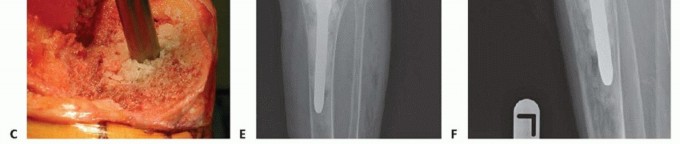

The preparation of the defect depends on the planned reconstruction method. For contained defects, the sclerotic margins of the cavity are burred or drilled to expose a vascular bed capable of supporting graft incorporation. For uncontained defects slated for structural allografting, the host bone is typically prepared with a flat planar cut or a step cut to provide a stable, geometric seating surface for the allograft.

Impaction bone grafting is an excellent technique for managing large, contained metaphyseal defects (Anderson Orthopaedic Research Institute Type 2A and 2B). The technique relies on the viscoelastic properties of tightly packed cancellous bone to provide immediate mechanical stability.

Fresh frozen femoral head allografts are processed through a bone mill to create cancellous chips ranging from three to five millimeters in diameter. The medullary canal is plugged distally, and a trial stem is inserted to maintain the central alignment. The cancellous allograft is then introduced into the metaphyseal voids and vigorously impacted using specialized tamps and a mallet. The impaction process converts the loose chips into a dense, interlocking matrix. This process is repeated until the defect is completely filled and the graft bed is highly resistant to further impaction. The final revision tibial component is then cemented over the impacted graft, utilizing a diaphyseal stem to protect the graft from excessive shear forces during the biological incorporation phase.